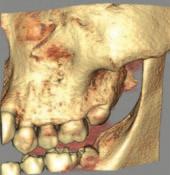

Journal of the Irish dental association by Th!nk Media - Issuu